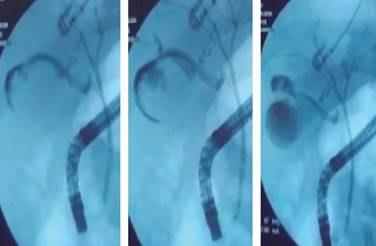

Continuando el protocolo de estudio, se decide iniciar la vía oral (cuatro días y 15 horas de evolución), se realiza colangiopancreatografía retrógrada endoscópica (CPRE), en la cual se reporta conducto biliar que comunica a colección pequeña adyacente a vesícula biliar (Figura 4). Sin embargo, al analizar las imágenes, se observó una disrupción de la pared de la vesícula biliar adyacente al parénquima hepático, documentando así la lesión de vesícula biliar.

Figura 4: Imágenes de la colangiopancreatografía retrógrada endoscópica, en la que se observa fuga de contraste en pared posterior de la vesícula hacia el parénquima hepático, con probable disección de la pared posterior.